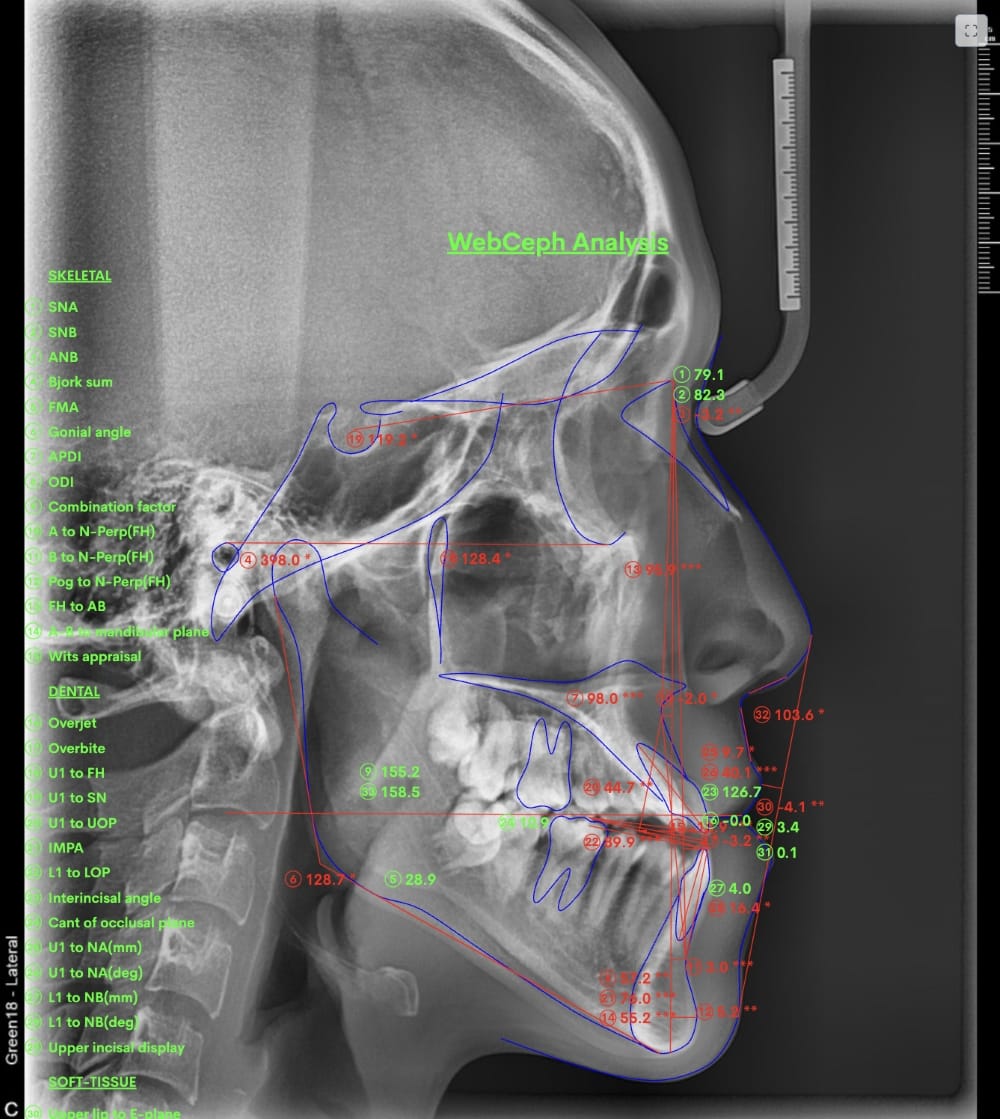

具体的には、口腔内写真やレントゲン写真、特にセファロX線写真を分析し、診断を行います。

例えばセファロX線写真での診断を行い上下の顎の位置のズレが大きいと判断した場合、歯列矯正のみでの治療は困難と判断し、外科的な手術をおすすめする場合もあります。

分析しますと

- 骨格的な上下あごの前後差は重度

- 噛み合わせの位置も下あごの奥歯が半分くらい前にズレていた

- 上の前歯が前に傾斜、下の前歯が内側に傾斜しているにもかかわらず、受け口

というケースで、外科的な処置も検討するようなケースでした。

骨格的なズレや奥歯の噛み合わせのズレもあり、重度の受け口でしたが、なんとか歯列矯正のみで受け口を改善できると診断し、治療を開始しました。

先ほどの2ケースと同じように、患者さまに外科的な手術の選択肢も提示しましたが、希望されず、横顔の変化はおそらく起こらないことを納得の上、治療をスタートいたしました。

今回のケースも奥歯の移動量が大きいため、マウスピースだけでは難しいと判断し、カリエールとよばれる装置を補助的に使用し、上下の噛み合わせの前後関係を整えることで、手術を行わずに機能面と見た目の両方が改善することにしました。